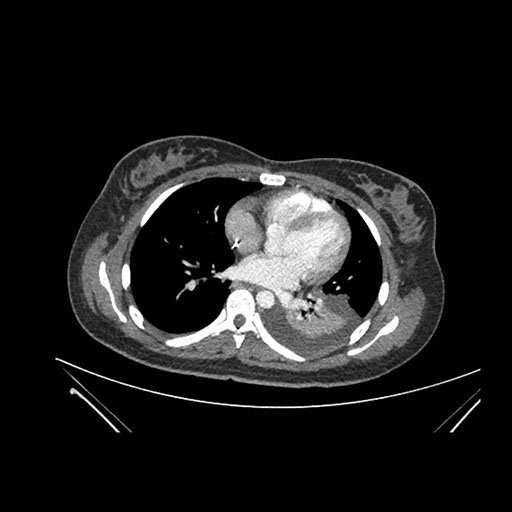

Axial Arterial

Axial Venous